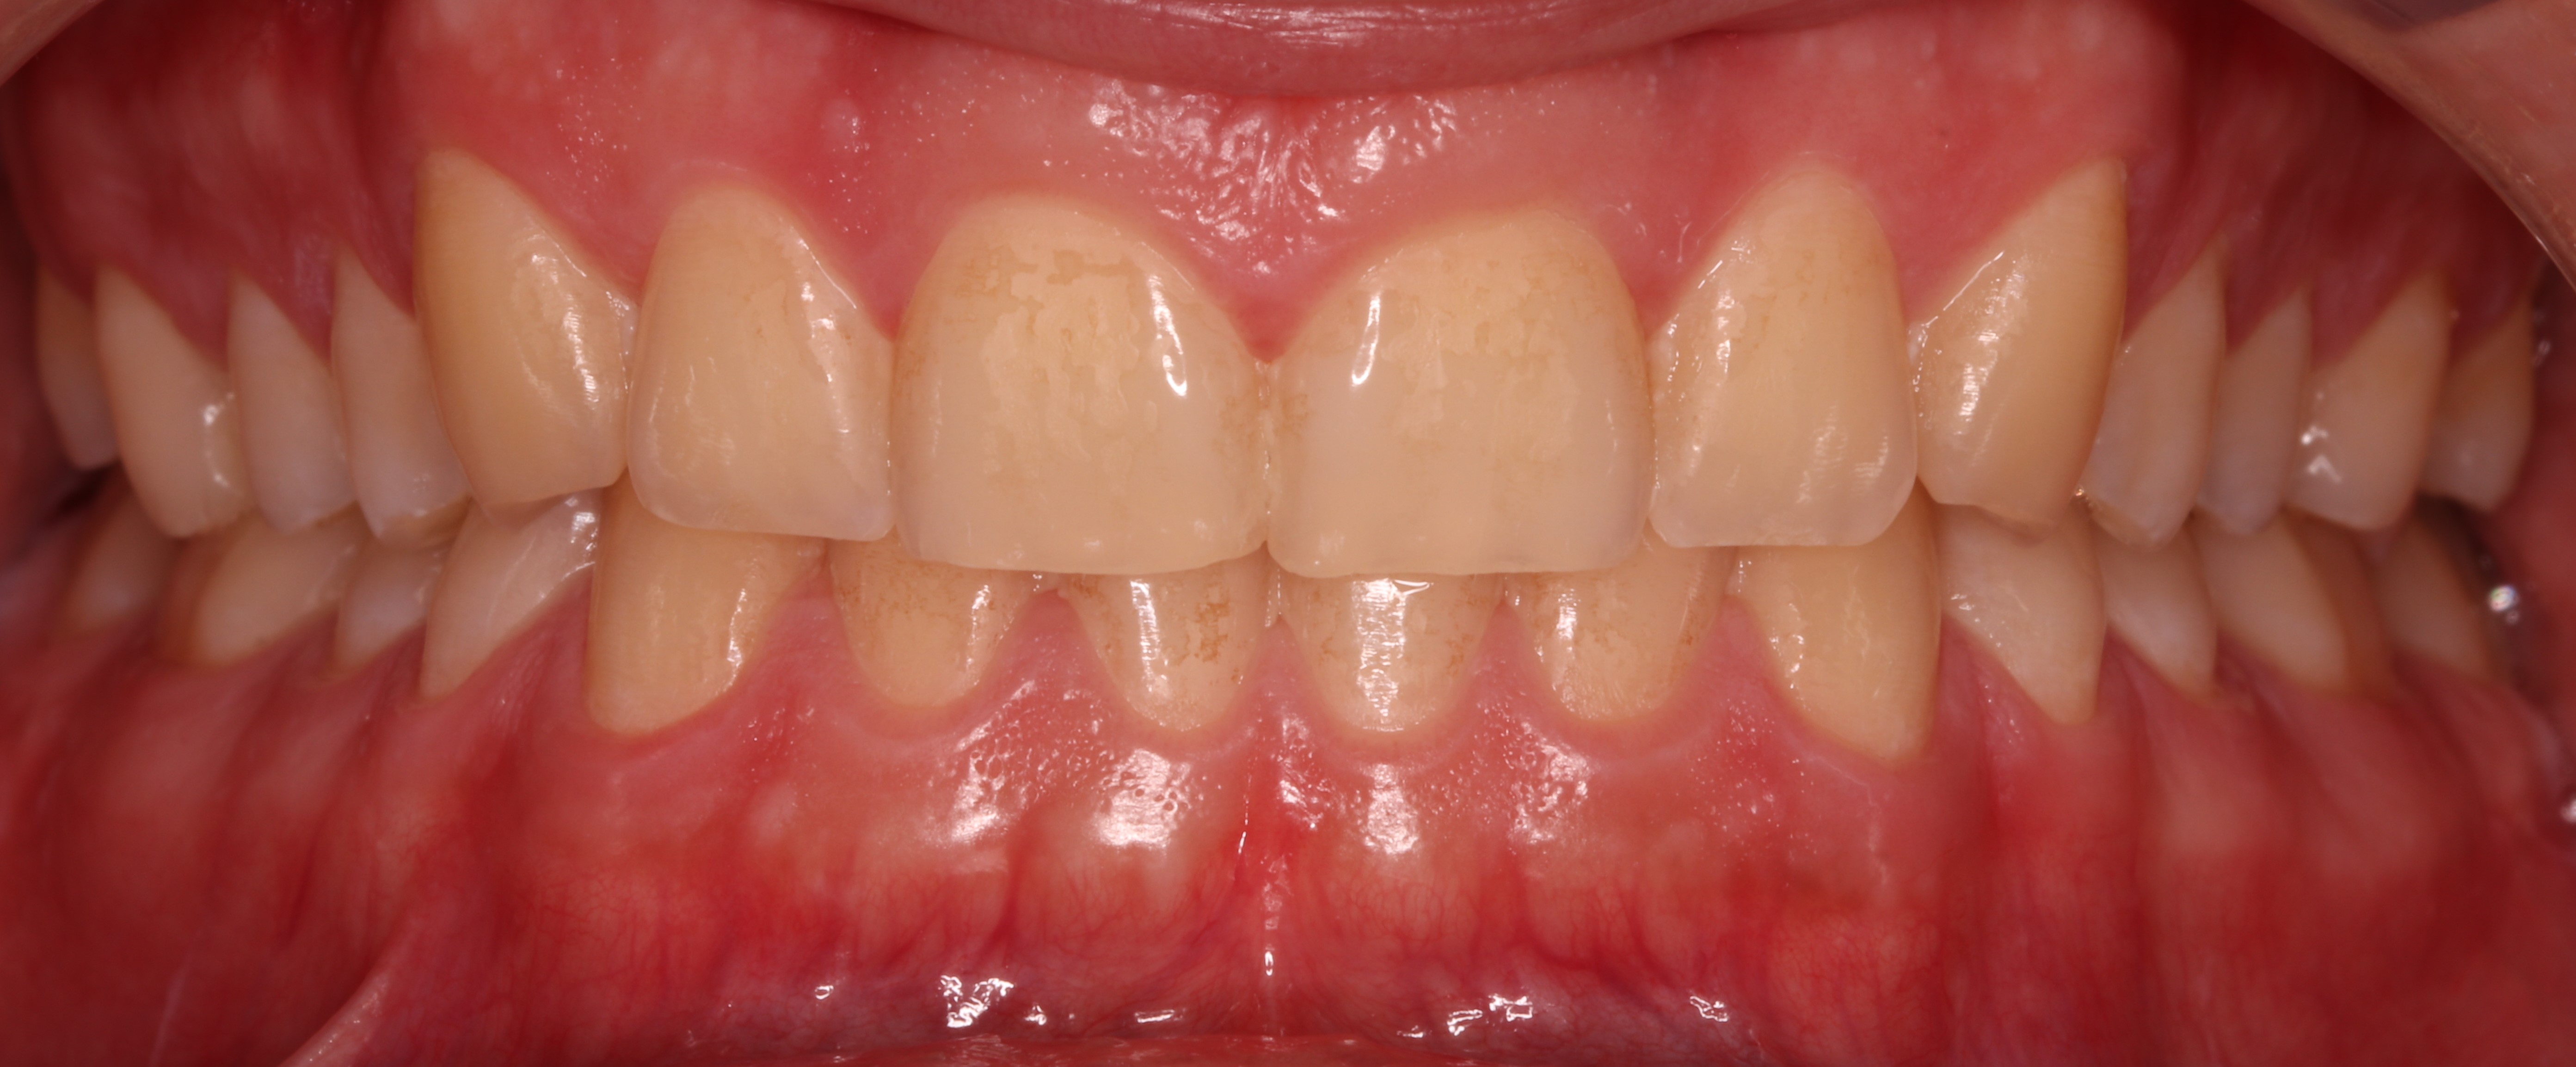

Pacjent, 18 lat, został skierowany w celu leczenia zachowawczego przed planowanym leczeniem ortodontycznym i odbudową startych zębów. W badaniu klinicznym stwierdzono niedostateczną higienę jamy ustnej – osad i złogi miękkie w przestrzeniach międzyzębowych, uogólnioną erozję szkliwa, starcie oraz liczne ogniska próchnicy pierwotnej zlokalizowane na powierzchniach stycznych zębów bocznych (ryc. 1‑4).

Ryc. 1. Sytuacja początkowa.